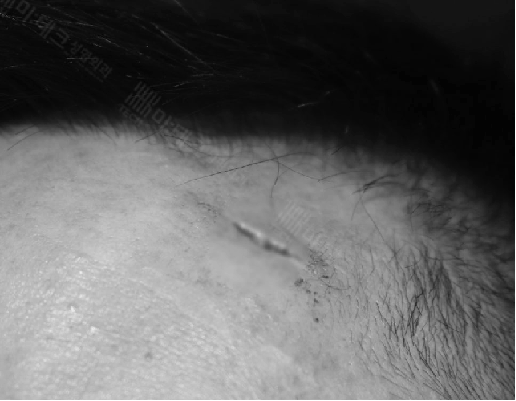

수술 전 240223

상처를 그냥 봉합하는 것보다는 변연절제술을 시행하면 조금 더 흉터를 깔끔하게 만들 수 있습니다.

상처를 제대로 확인해 보면 이마의 근육층까지 손상이 있을 수 있습니다.

근봉합이 필요한 경우라고 하겠습니다.

봉합한 사진만 봐서는 변연절제술을 했는지, 근봉합을 했는지, 환자로서는 알 길이 없죠.